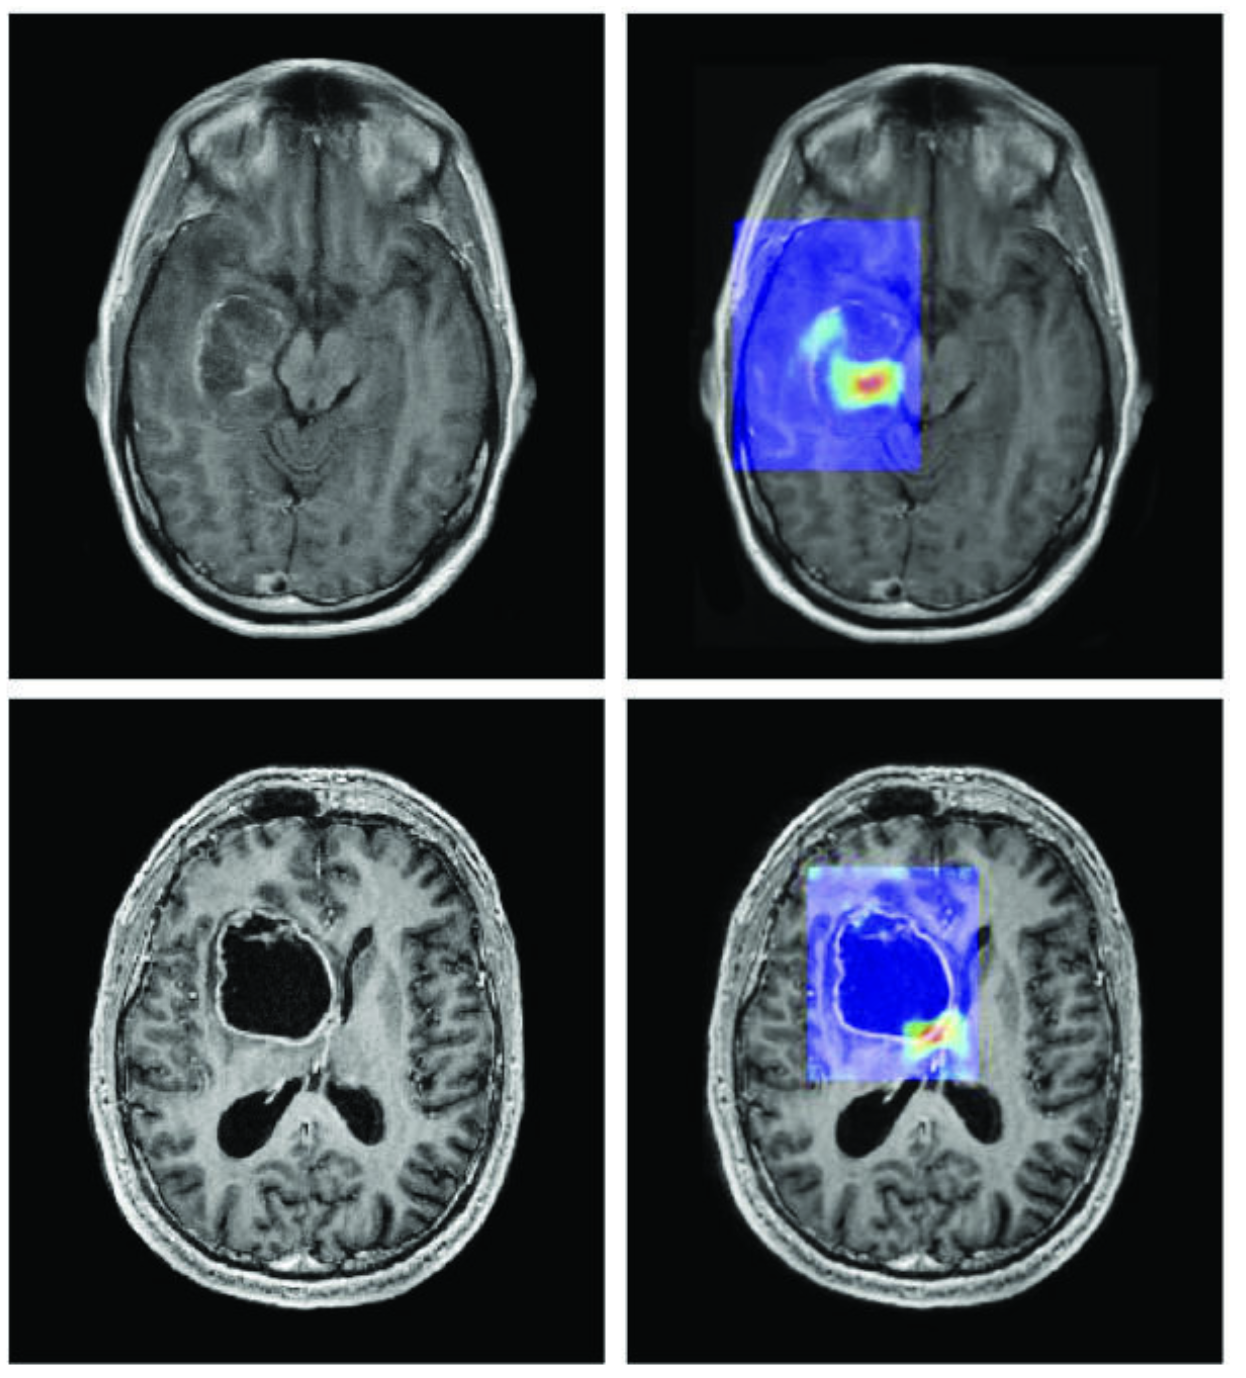

Image extracted from: CA Cancer J Clin March/April 2019. DOI: 10.3322/caac.21552. License: CC BY 4.0.

Three concrete situations already illustrate this effective coexistence between humans and AI. In medicine, AI systems analyze thousands of X-rays in seconds to detect early signs of cancer [1]; but it is the doctor who interprets the patient's clinical context, engages in dialogue with them, and decides on the appropriate treatment protocol: AI accelerates diagnosis, but the human bears the responsibility and meaning. In industry, car manufacturers use AI to control quality on production lines [2], identifying defects invisible to the naked eye; yet it is the engineers who design the processes, adjust tolerance thresholds, and make decisions when a problem falls outside the algorithm’s predicted framework. Finally, in scientific research, AI developed by DeepMind has enabled the prediction of the three-dimensional structure of over two hundred million proteins [3], a task that would have taken centuries for researchers alone; but it is biologists and chemists who formulate hypotheses, design experiments, and transform these predictions into treatments or new materials. In each of these cases, the lesson is the same: AI does not replace humans; it multiplies their capacity for action.